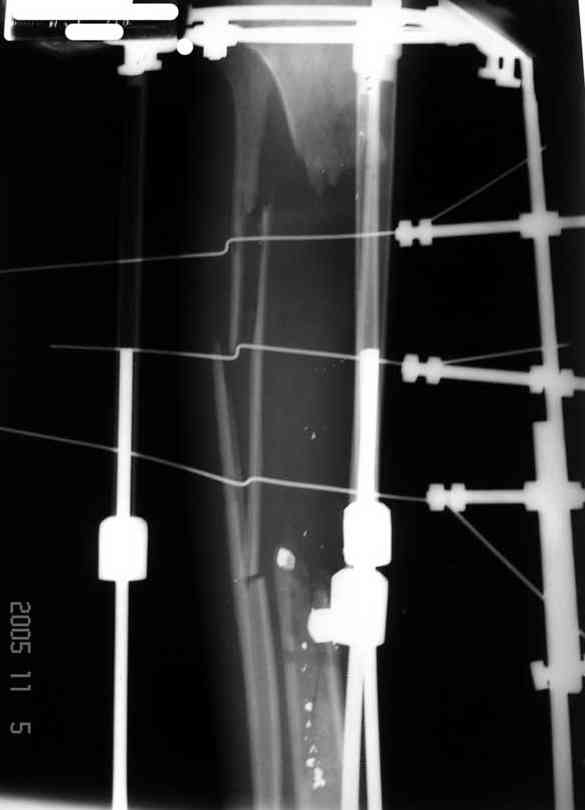

Пациент 19 лет, производственная травма, придавлен тяжелой плитой. Политравма (ISS 21).

1 - рентгенограмма (прошу прощения за качество) при поступлении;

2 - внешний вид голени;

Произведено ПХО, acute shortening (5 см), фиксация стержневым аппаратом Hoffman.

3,4 - через 4 недели наложен спице-стержневой аппарат, произведена остеотомия большеберцовой кости в верхней трети, раны зажили, проводилась дистракция в аппарате.